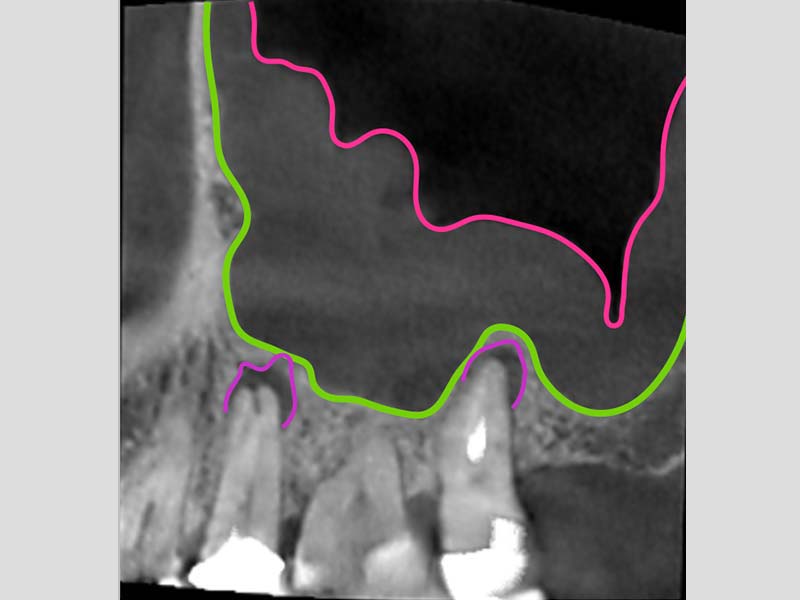

圖例為案例分享:

粉:感染增生的鼻竇黏膜

綠:原本的鼻竇範圍

紫:牙齒跟監感染,進入鼻竇

術前的電腦斷層